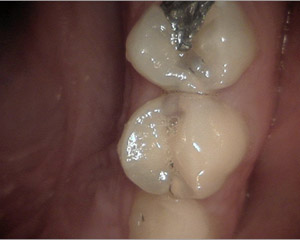

Normalment, amb la exploració clínica s'aprecien molts signes de malalties del pacient: càries, inflamació de genives, sagnat de genives, leucoplàsies, ulceracions, etcètera. Tot així, hi han moltes vegades que el diagnóstic no es pot realitzar, o aquest pot ser erroni si no es realitzen les proves complementàries adients. Al nostre centre disposem de potents càmeres intraorals que ens permeten identificar petites lesions de les dents (fisures, fractures, etc) que d'altre manera passarien desapercebudes.

caries1 caries2 caries3 caries4

A més, és molt important la realització de radiografies de dignòstic, tant a la primera visita com a les futures revisions, ja que el major nombre de les càries comencen als punts de contacte entre les dents o queixals, i aquests són innaccesibles visualment amb una exploració convencional.